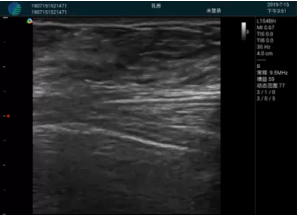

可視化甲狀腺穿刺引導(dǎo)

頸動(dòng)脈血流充盈飽滿,無外溢

肝內(nèi)血管顯示清晰,血流敏感無外溢

病例二:

甲狀腺囊性結(jié)節(jié),囊壁鈣化,透聲好

甲狀腺囊性占位

2001年美國健康護(hù)理研究和質(zhì)量監(jiān)督局(AHRQ)批準(zhǔn)了一項(xiàng)關(guān)于提高患者安全性的報(bào)告,建議:在頸內(nèi)靜脈中心置管術(shù)時(shí)使用超聲引導(dǎo)。此后超聲引導(dǎo)穿刺被用于幾乎所有的急診穿刺操作,尤其是血管穿刺。

便攜超聲在急診穿刺中的應(yīng)用:

* 提高了穿刺成功率

* 減少了穿刺損傷及并發(fā)癥

* 縮短了操作時(shí)間

* 減輕了患者痛苦